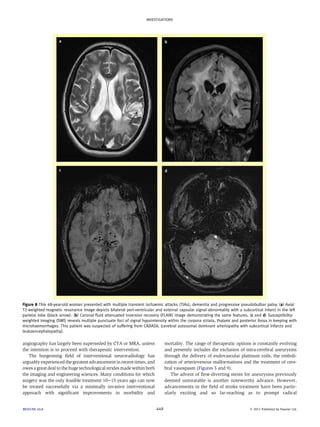

Figure 7 This 33-year-old man presented with rapidly progressive dementia. (a) Axial T2-weighted image at the level of the basal ganglia demonstrates

bilateral subtle signal hyperintensity involving the caudate and lentiform nuclei and thalami. (b) Axial fluid attenuated inversion recovery (FLAIR) image

demonstrates subtle cortically based signal hyperintensity involving the para-sagittal frontal lobes and peri-rolandic regions (arrows). (c and d) Axial

diffusion-weighted image (DWI) and apparent diffusion coefficient (ADC) map respectively: hyperintense change is seen within the basal ganglia and

thalami bilaterally with corresponding hypointensity on ADC; the appearances thus signify diffusion restriction. These are hallmark changes seen in

CreutzfeldteJakob disease (CJD).